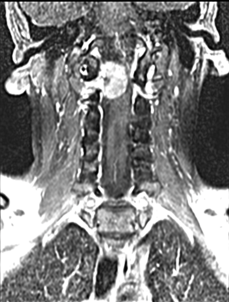

¿COMO SE DIAGNOSTICA UN TUMOR ESPINAL?

Si se sospecha un tumor espinal es recomendable realizar una resonancia magnética con contraste de la zona afectada de la columna vertebral y una vez identificado obtener una muestra del tejido del tumor para un análisis histopatológico específico.